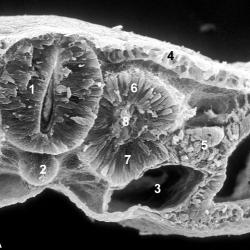

Эмбриология и внезародышевые органы

Эмбриология

Плацента

Оплодотворение

Гаструляция

Имплантация

Плацентация

Органогенез

Провизорные органы

Амнион

Хорион

Желточный мешок

Аллантоис